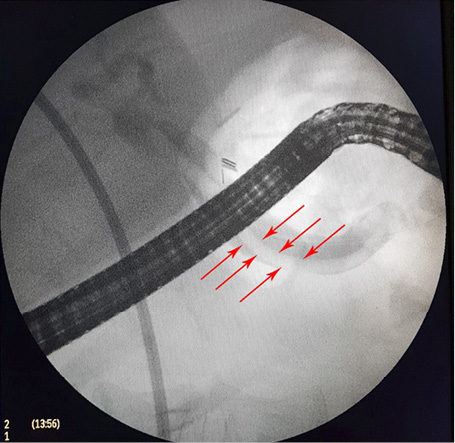

4 pav. ERC vaizdas: askaridės šešėlis BTL (pažymėta rodyklėmis)

5 pav. ERC vaizdas: BTL šešėlis pašalinus askaridę (pažymėta rodyklėmis)

Pacientei įtarta pilvo skausmų priežastis – tulžies latakų akmenligė, nesant mechaninės geltos. Priimtas sprendimas atlikti duodenoskopiją ir ERC tyrimą. Duodenoskopijos metu įvertinta, kad papilla Vateri yra po PST procedūros. Kontrastavus BTL, pastebėtas >5 cm ilgio 4 mm skersmens prisipildymo defektas lygiais kontūrais. Naudojant Dormia krepšelį, iš tulžies latako pašalintas prisipildymo defektas – askaridė (3–5 pav.). Atlikus procedūrą, pacientės sveikatos būklė pagerėjo, pilvo skausmas regresavo, nesikartojo. Papildomai atlikta dehelmintizacija mebendazolu, antihelmintiniu vaistiniu preparatu („Vermox“).